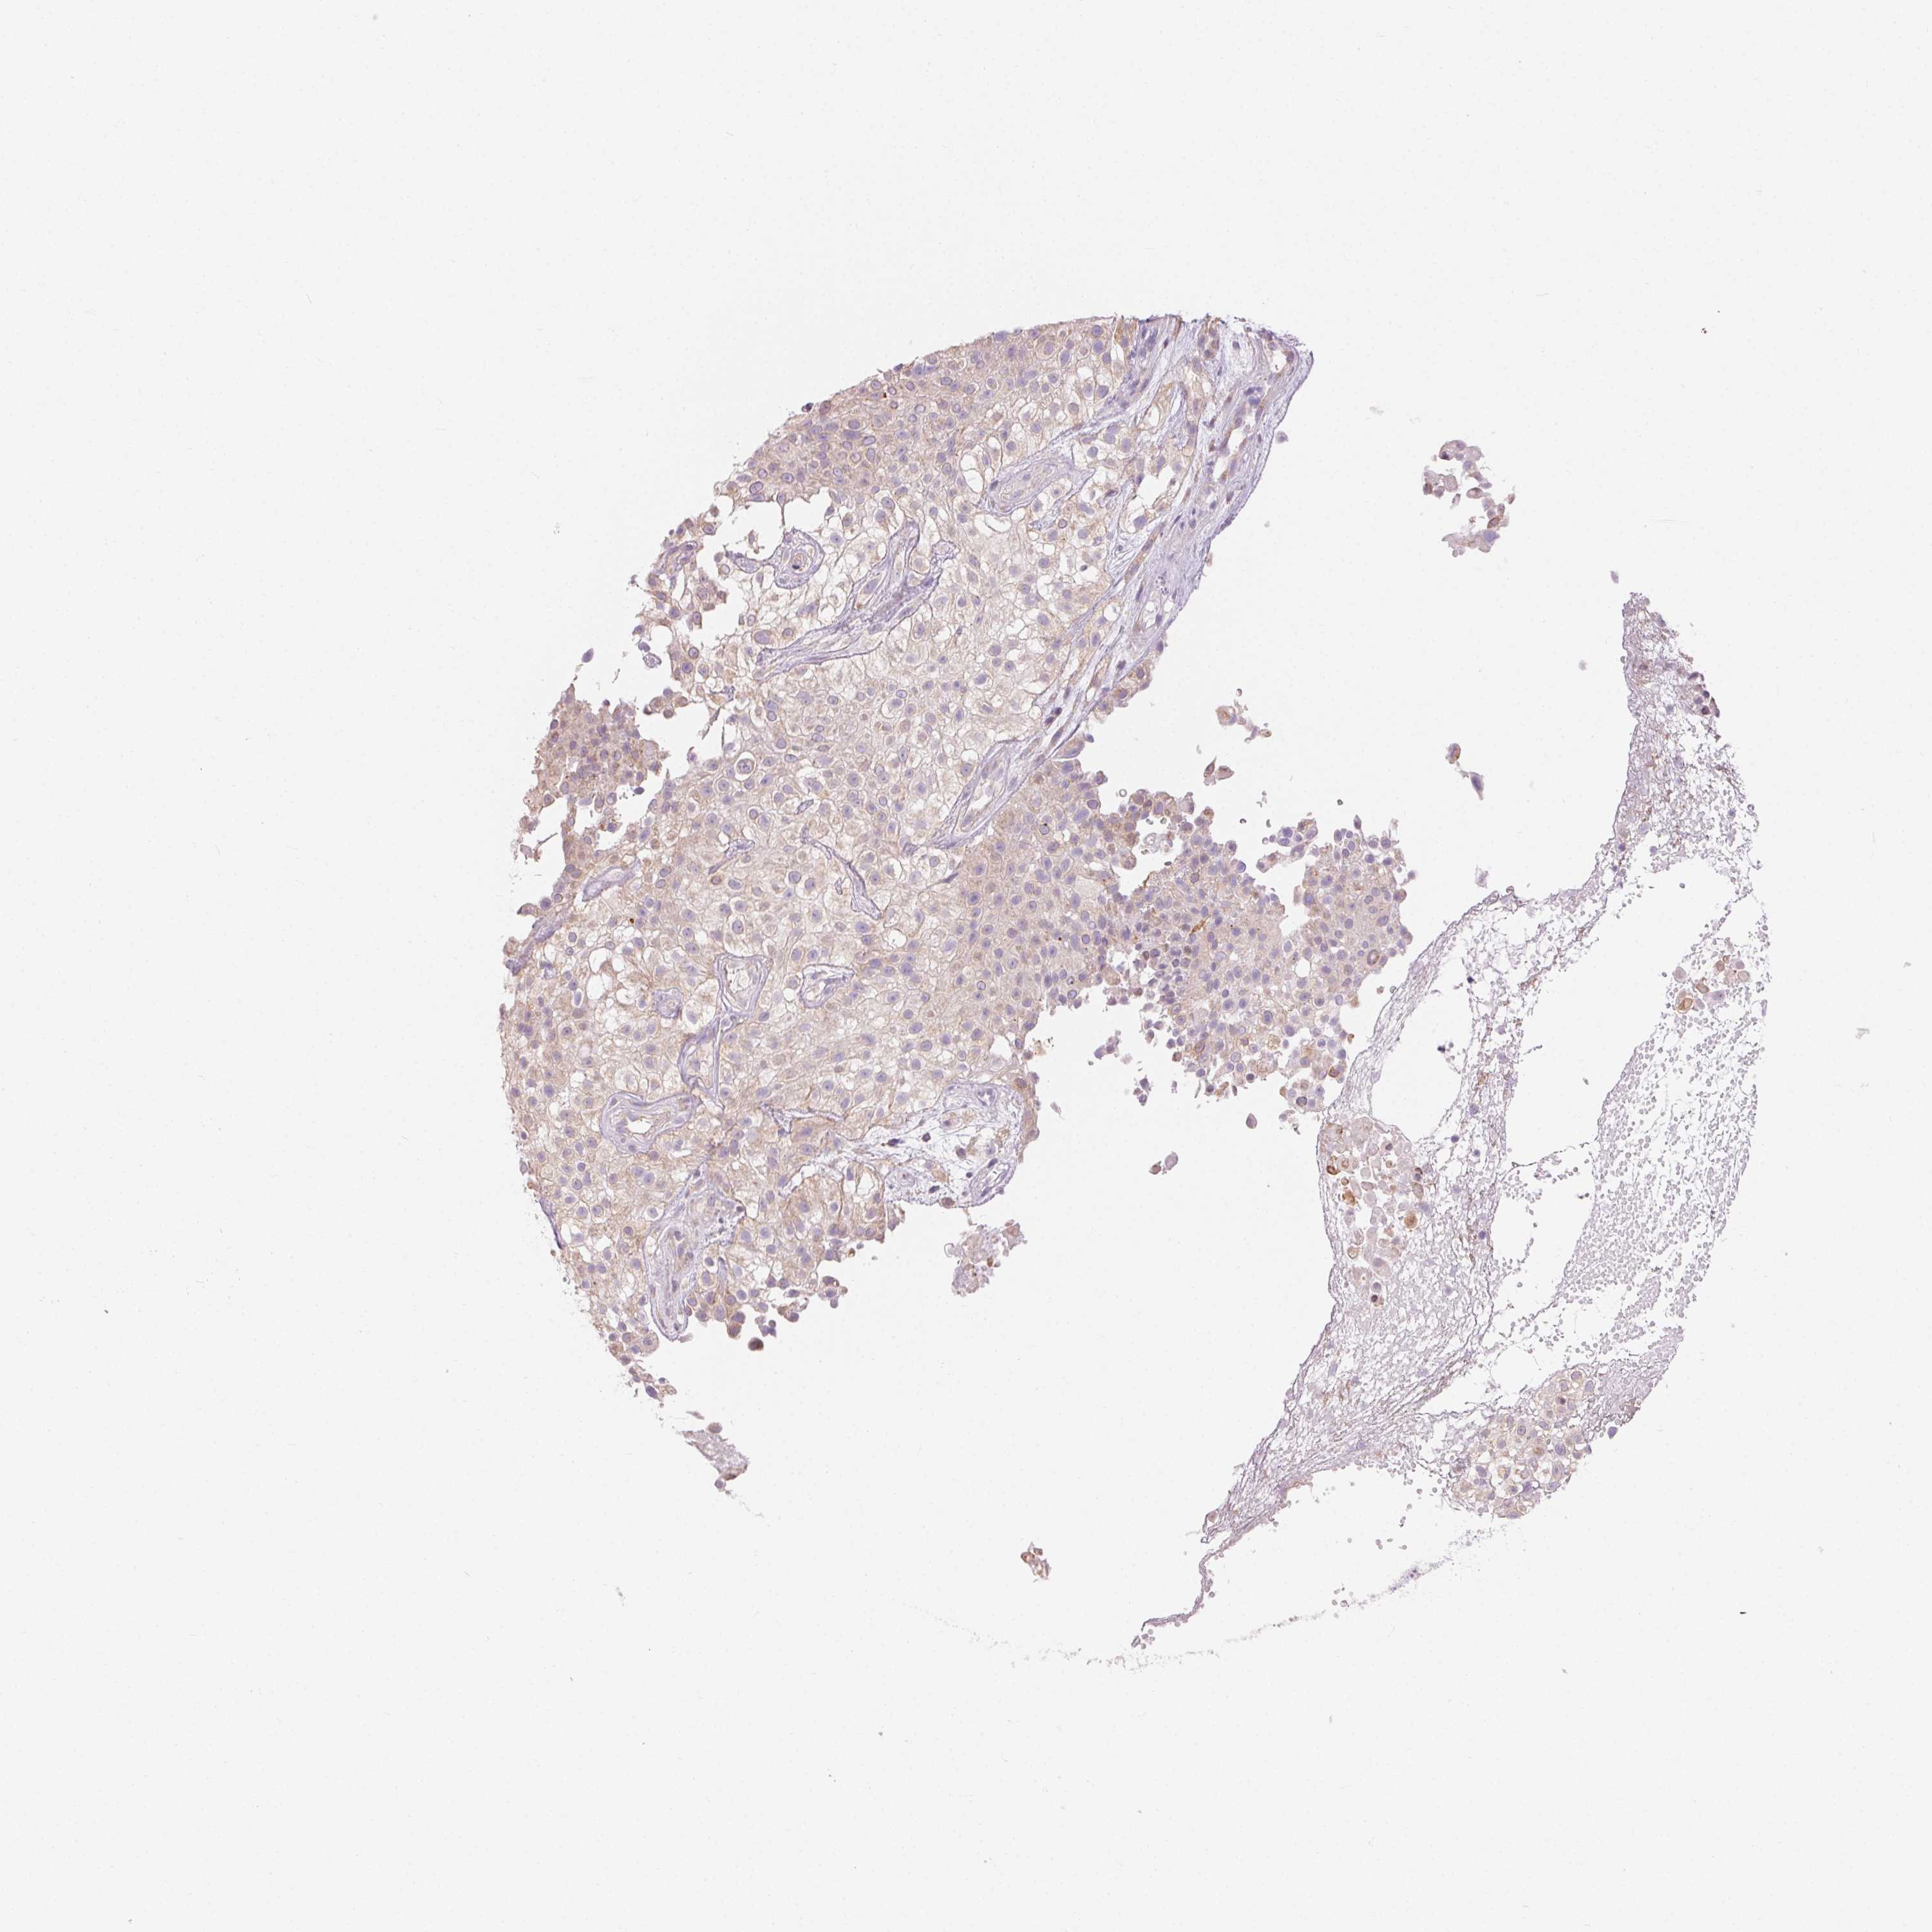

UROTHELIAL CANCER - Protein expressioni

A mouse-over function shows sample information and annotation data. Click on an image to view it in a full screen mode. Samples can be filtered based on level of antibody staining by selecting one or several of the following categories: high, medium, low and not detected. The assay and annotation is described here.

Note that samples used for immunohistochemistry by the Human Protein Atlas do not correspond to samples in the TCGA dataset.

Antibody stainingi

Antibody staining in the annotated cell types in the current human tissue is reported as not detected, low, medium, or high, based on conventional immunohistochemistry profiling in selected tissues. This score is based on the combination of the staining intensity and fraction of stained cells.

Each image is clickable and will lead to virtual microscopy that enables deeper exploration of all samples and also displays staining intensity scores, fraction scores and subcellular localization as well as patient and tissue information for each sample.

Antibody HPA016843

Antibody CAB034017

Staining

High

Medium

Low

Not detected

Intensity

Strong

Moderate

Weak

Negative

Quantity

>75%

75%-25%

<25%

None

Location

Nuclear

Cytoplasmic/membranous

Cytoplasmic/membranous,nuclear

Urothelial carcinoma, High grade

Urothelial carcinoma, NOS

Urothelial carcinoma, Low grade